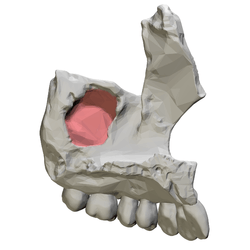

Left maxilla, medial view. Maxillary sinus shown in red. | |